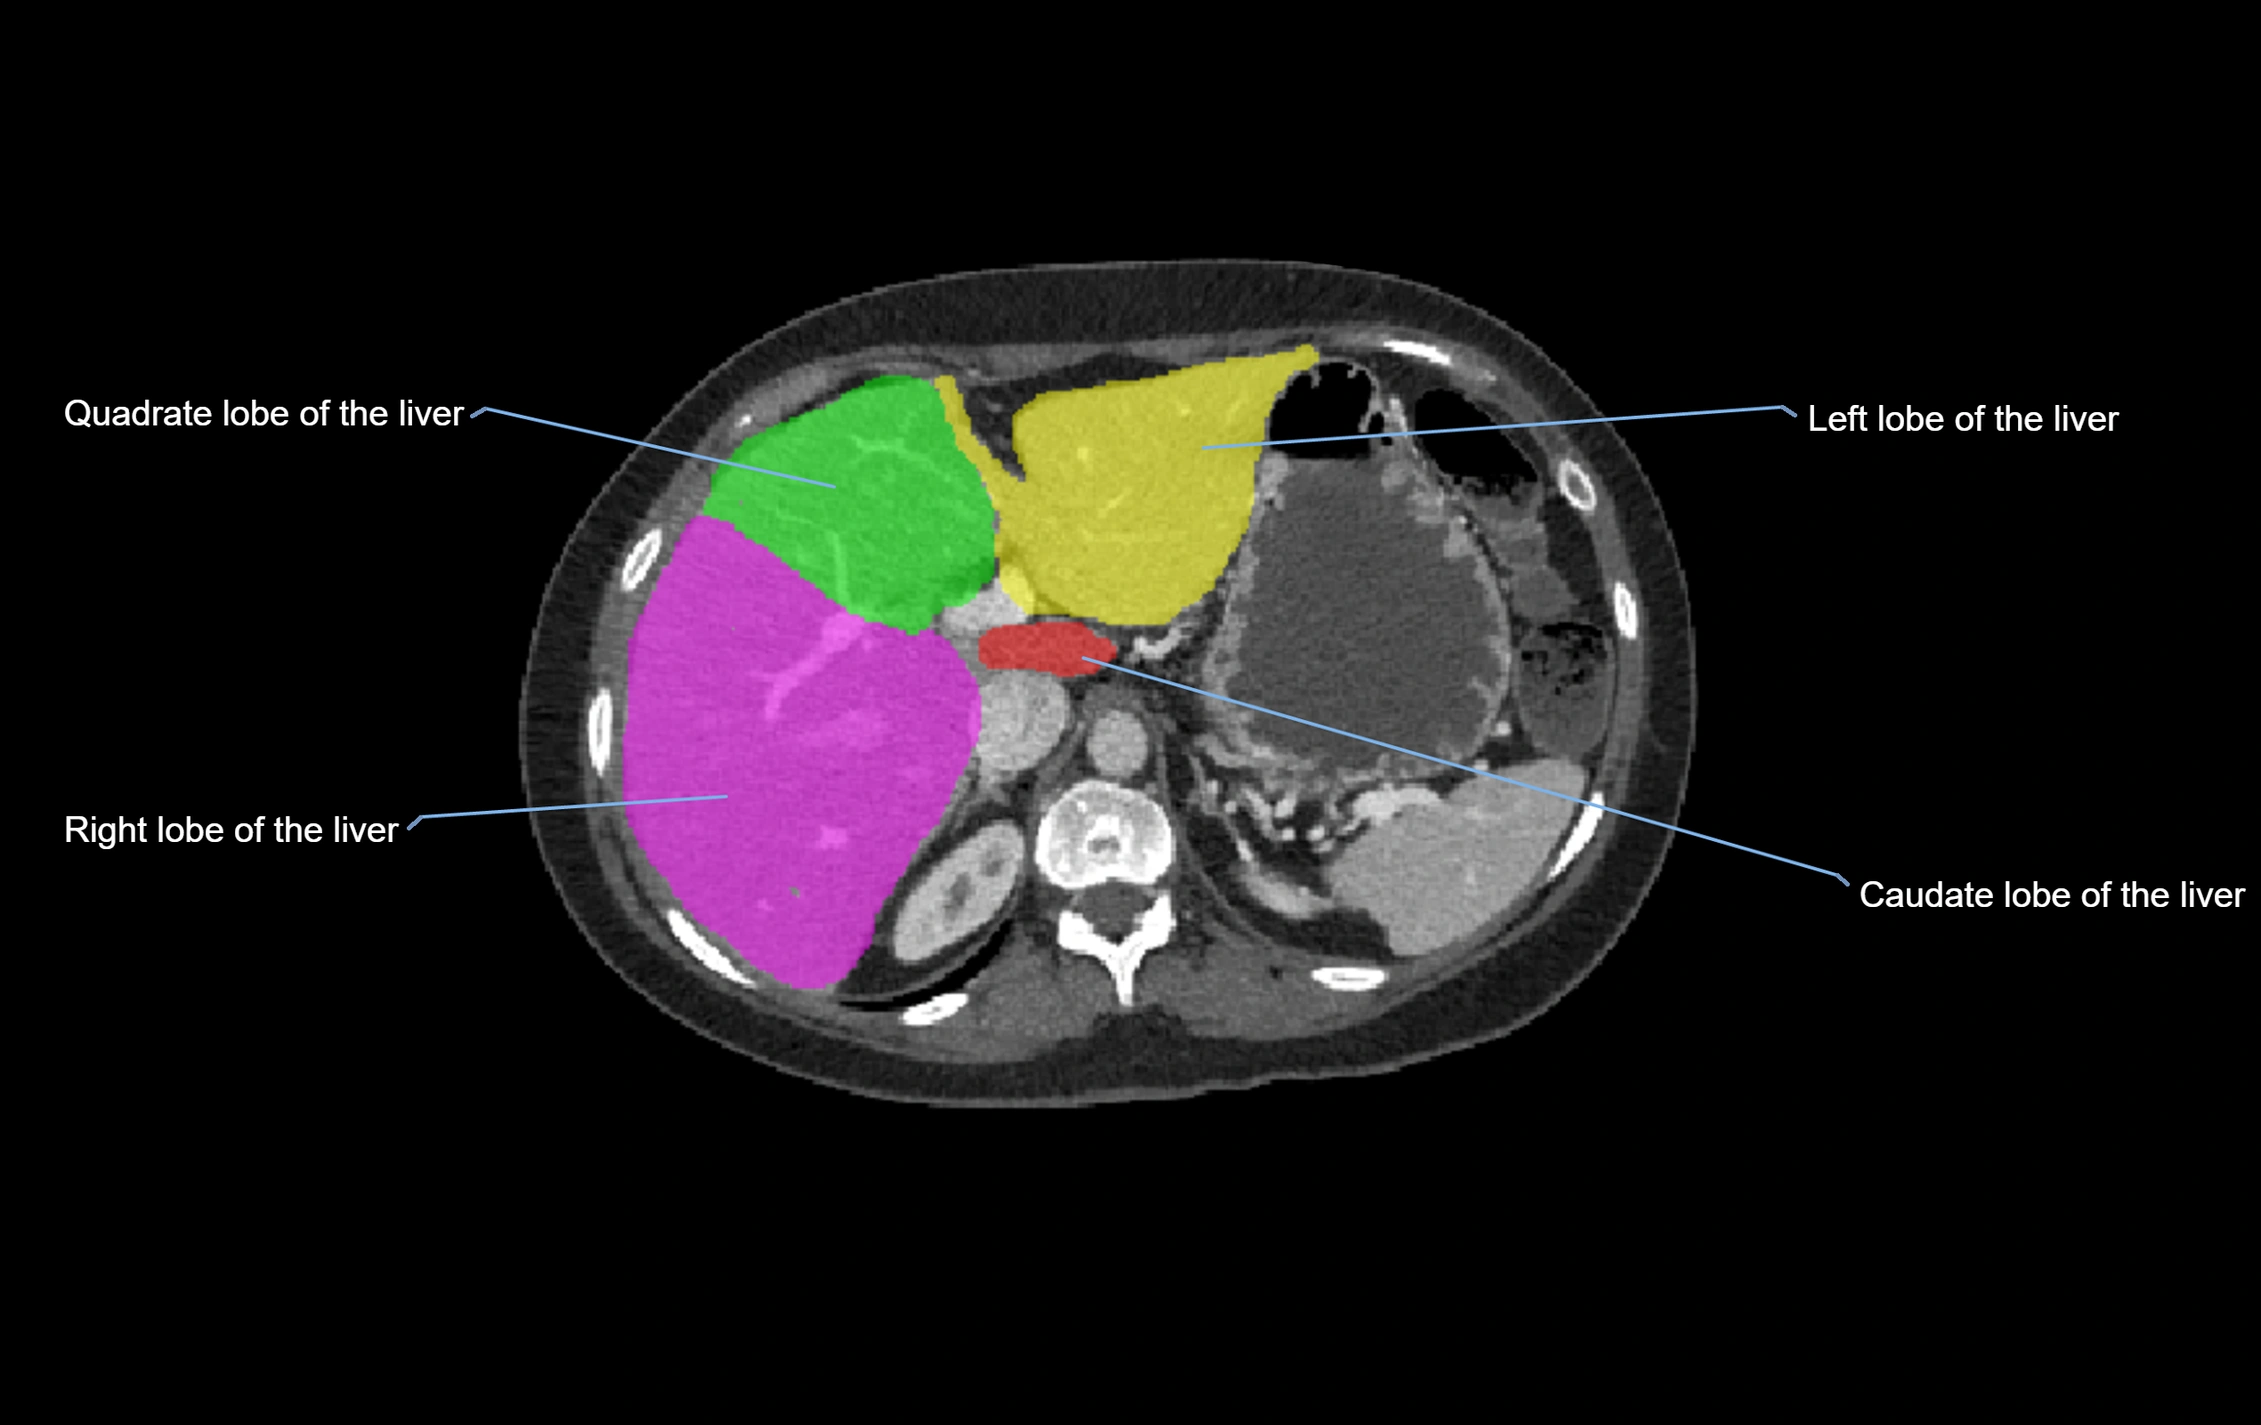

Caudate lobe of liver

The caudate lobe of the liver is a distinct anatomical subdivision of the liver, designated as segment I in Couinaud’s classification. It lies on the posterior surface of the liver, between the fissure for the ligamentum venosum (left boundary) and the groove for the inferior vena cava (IVC) (right boundary). Superiorly, it is related to the posterior liver surface, and inferiorly it is separated from the left lobe by the porta hepatis.

The caudate lobe is unique because it receives dual portal venous and arterial inflow from both the right and left portal veins and hepatic arteries. It also has independent venous drainage directly into the IVC via multiple small hepatic veins, unlike other lobes that drain through the three main hepatic veins.

This anatomical autonomy makes the caudate lobe especially significant in liver surgery, transplantation, and hepatic venous outflow obstruction syndromes (e.g., Budd–Chiari syndrome). Enlargement of the caudate lobe is a characteristic imaging feature in chronic liver disease and cirrhosis.

CT Appearance

CT Pre-Contrast:

• Caudate lobe appears as a soft-tissue density, isodense to the rest of the liver

• Enlargement may be appreciated in cirrhosis or Budd–Chiari syndrome

CT Post-Contrast:

• Homogeneous enhancement in the portal venous phase, similar to rest of liver

• Independent venous drainage into the IVC may be visualized

• Lesions follow characteristic CT enhancement patterns (HCC: arterial hyperenhancement with washout; hemangiomas: peripheral nodular enhancement with centripetal fill-in)

CT Venous Phase (functional significance):

• Caudate lobe often enhances relatively more than other lobes in Budd–Chiari syndrome, due to preserved venous outflow

CT Image

image